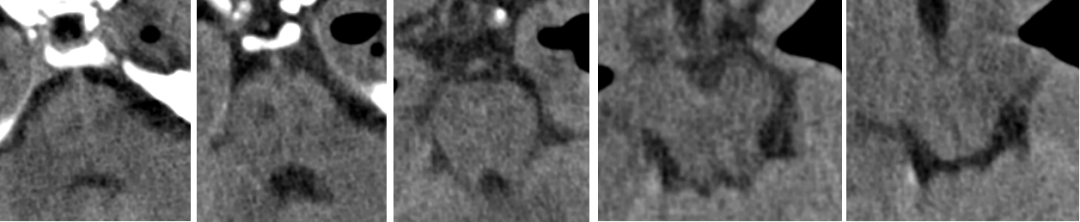

2014-11-18 0am CT

2014-11-18 10am CT

2014-11-19 CT

2014-11-20 CT